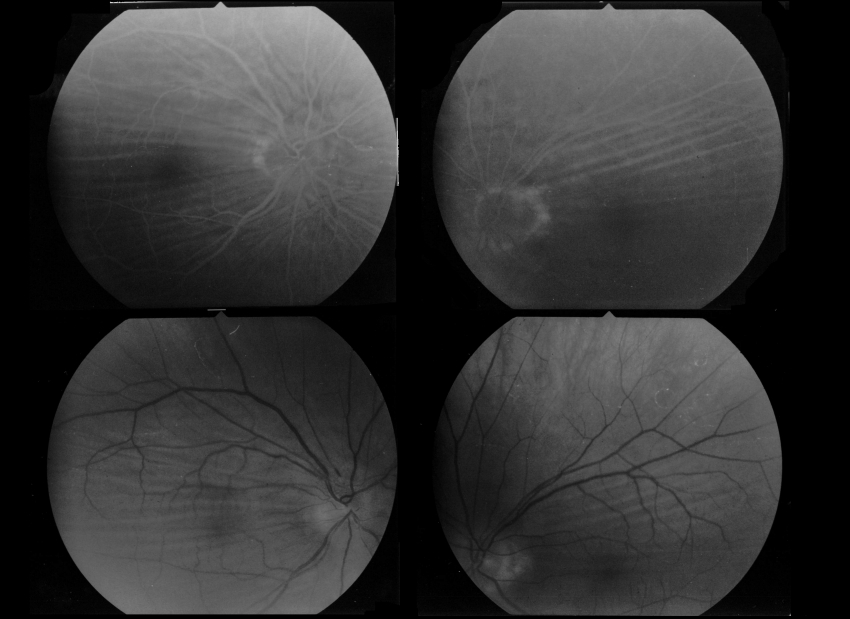

원시는 물체의 상이 망막 뒤에 맺혀 시야가 흐려 보이는 굴절 이상의 일종이다. 모양체근의 조절 능력 저하나 안구 길이 단축이 주요 원인이며, 임상적 분류, 심각도, 조절 상태에 따라 다양하게 분류된다. 치료 방법으로는 안경이나 콘택트 렌즈 착용, 라식, 라섹과 같은 시력 교정술, 인공 수정체 삽입술 등이 있다. 원시는 급성 폐쇄각 녹내장, 녹내장, 사시 등의 합병증을 유발할 수 있으며, 소아 원시는 약시의 원인이 되기도 한다. 노화에 따른 조절력 저하로 원시 증상이 나타나는 것을 노안이라고 한다.

원시 진단은 검영기 또는 자동 굴절 검사(객관적 굴절 검사)를 사용하거나, 시험용 안경테 또는 프롤로프터를 사용하여 주관적인 검사를 통해 이루어진다. 비정상적인 구조와 생리를 확인하기 위한 보조 검사로는 세극등 검사가 있는데, 이 검사는 각막, 결막, 전방, 그리고 홍채를 검사한다.[15][16]